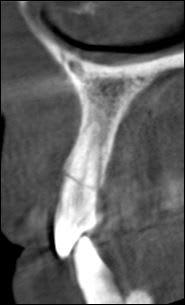

Je le vois en décembre 15j après le trauma pour faire le bilan. Puis un collage /contention sur 22 fracturée et cone beam. Brossage compliqué car grosses douleurs

extraction implant 3mmx14

le petit bonus la fracture de l'apex de 11 jusqu'ici passée inaperçue vu les douleurs de l'autre côté.